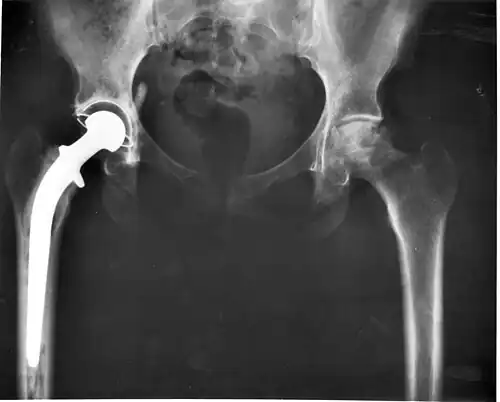

Heupimplantaat

Röntgenfoto van een typisch heupimplantaat in de rechterheup (op de foto links): de metalen heupkop is verankerd in het bovenbeensbot, terwijl in het bekken de heupkom vervangen is door een exemplaar van wit plastic (op de foto transparant)